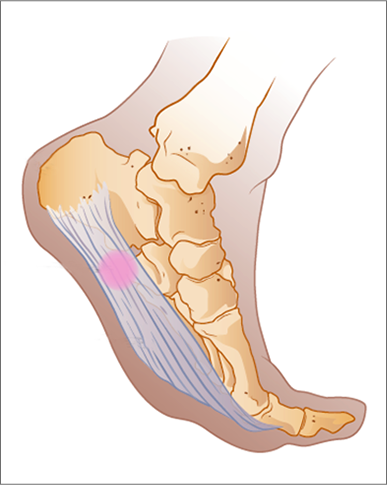

초기에는 밤에만 불편함을 느끼다가 점점 지속 시간도 늘어납니다.3. 족저근막염

발바닥 통증의 대표 질환으로,

발뒤꿈치에서 발바닥 전체로 이어지는 근막에 염증이 생기며

걷거나 서 있을 때 발바닥이 뜨겁고 찌릿한 통증을 유발합니다.

특히 아침에 첫 발을 디딜 때 더 아픈 경우가 많아요.